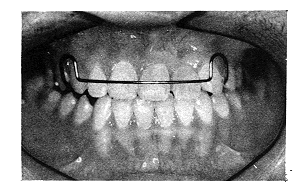

图2 治疗前牙合像

图3 治疗中反合解除合像

图4 治疗后截入有暂时义齿的保持器合像